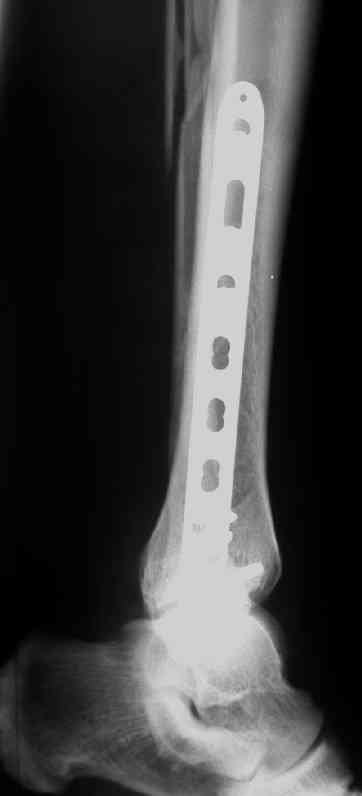

Выполнил MIPO предизогнутой метафизарной LCP

В этом случае остеосинтез выполнялся малоинвазивно и я не добивался абсолютной стабильности преднамеренно. Стабильность относительная и ст. её зависит от механических свойств импланта;возможно, нужно было взять длиннее пластину, увеличив её рабочую длину

Все справедливо для оскольчатого перелома, когда вы не добиваетесь анатомичной репозиции. При простом переломе адекватной будет анатомичная репозиция, и она у Вас получилась закрыто. Если Вы изначально предполагали относительную стабильность, то штифт позволил бы более раннюю и агрессивную реабилитацию

В последствии стал выполнять мостовидную фиксацию не только при оскольчатых переломах, но и при простых, прооперировал около 30 голеней, сращение наступило у всех периостальной мозолью.